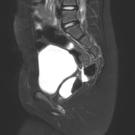

A 73-year-old man presented to the emergency department with constipation. He reported that he was unable to have a bowel movement for 5 days prior to presentation, despite the use of home enemas,...

01/12/2025